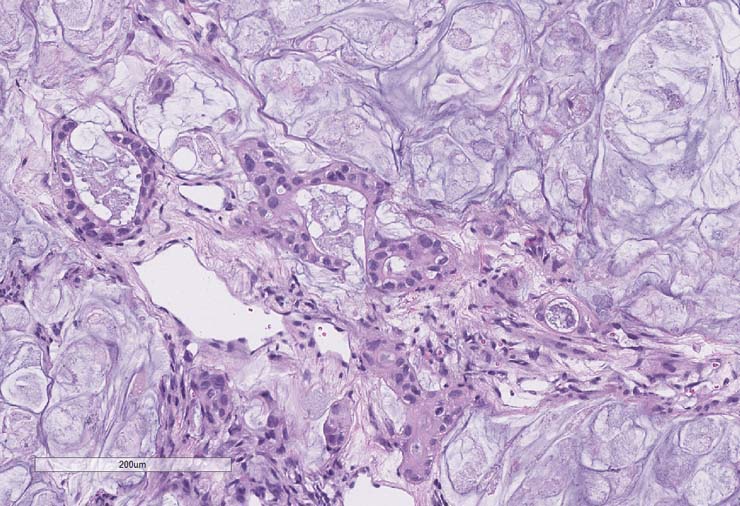

P0, P1 pathology consistent with adenocarcinoma. P2 pathology consistent with mucinous adenocarcinoma.

P0 tumor F240 for PDX model TM00351 stained for H&E.

P1 tumor F239 ID003 for PDX model TM00351 stained for H&E.

P2 tumor F239 ID011 for PDX model TM00351 stained for H&E.